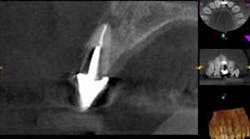

A 60-year-old male patient presented with a buccal swelling in the maxillary left anterior. Clinically the patient had a three-unit bridge connecting Nos. 7–9 (figure 1). The patient was happy with the esthetics and wanted to save his natural dentition. The recommendation was made to take a narrow-field CBCT scan to evaluate No. 7 in three dimensions. The CBCT scan showed that the apical disease had led to root resorption at the apical third of tooth No. 7 on the distal root surface (figure 2). This was invaluable information that allowed me to make the best approach to the root surface while keeping the osteotomy as small as possible. It also allowed me to have a three-dimensional view of No. 7 before even beginning the surgery, which helped to aid in proper root resection to conserve as much sound tooth structure as possible.

After root resection, root end prep and the placement of biologically compatible root end filling, the osteotomy was grafted (figure 3). Because of the size of the apical disease, along with the large cast post and the resorption, traditional nonsurgical retreatment was not a viable option for long-term success. With the aid of the CBCT imaging, it was already noted where the root end filling needed to be placed not only to seal the distal defect but to seal the true apical terminus.